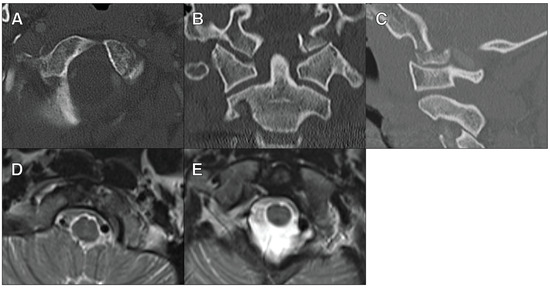

Only 3.6% (2/56) of the patients were managed with OC fusion for their OCF alone. The first patient was a 27-year-old female who presented after a motor vehicle collision with a right type III OCF and C1 lateral mass fracture. There was a slight coronal deformity seen on CT scans, and the MRI of her cervical spine demonstrated the disruption of the right alar ligament, tectorial membrane, and posterior atlantoaxial ligament (Figure 1). This patient underwent an O-C3 fusion.

Figure 1. A 27-year-old female who presented after a motor vehicle collision with a right type III OCF and C1 lateral mass fracture (A) The axial view of a CTA scan showing the right type III OFC. (B) The coronal view of a CTA scan showing the right type III OFC. (C) The sagittal view of a CTA scan showing the right type II OFC. (D) The axial view of an MRI T2 STIR sequence showing right alar ligament disruption. (E) The coronal view of an MRI T2 STIR sequence showing right alar ligament disruption. (F) The sagittal view of an MRI T2 STIR sequence showing posterior ligamentous disruption.